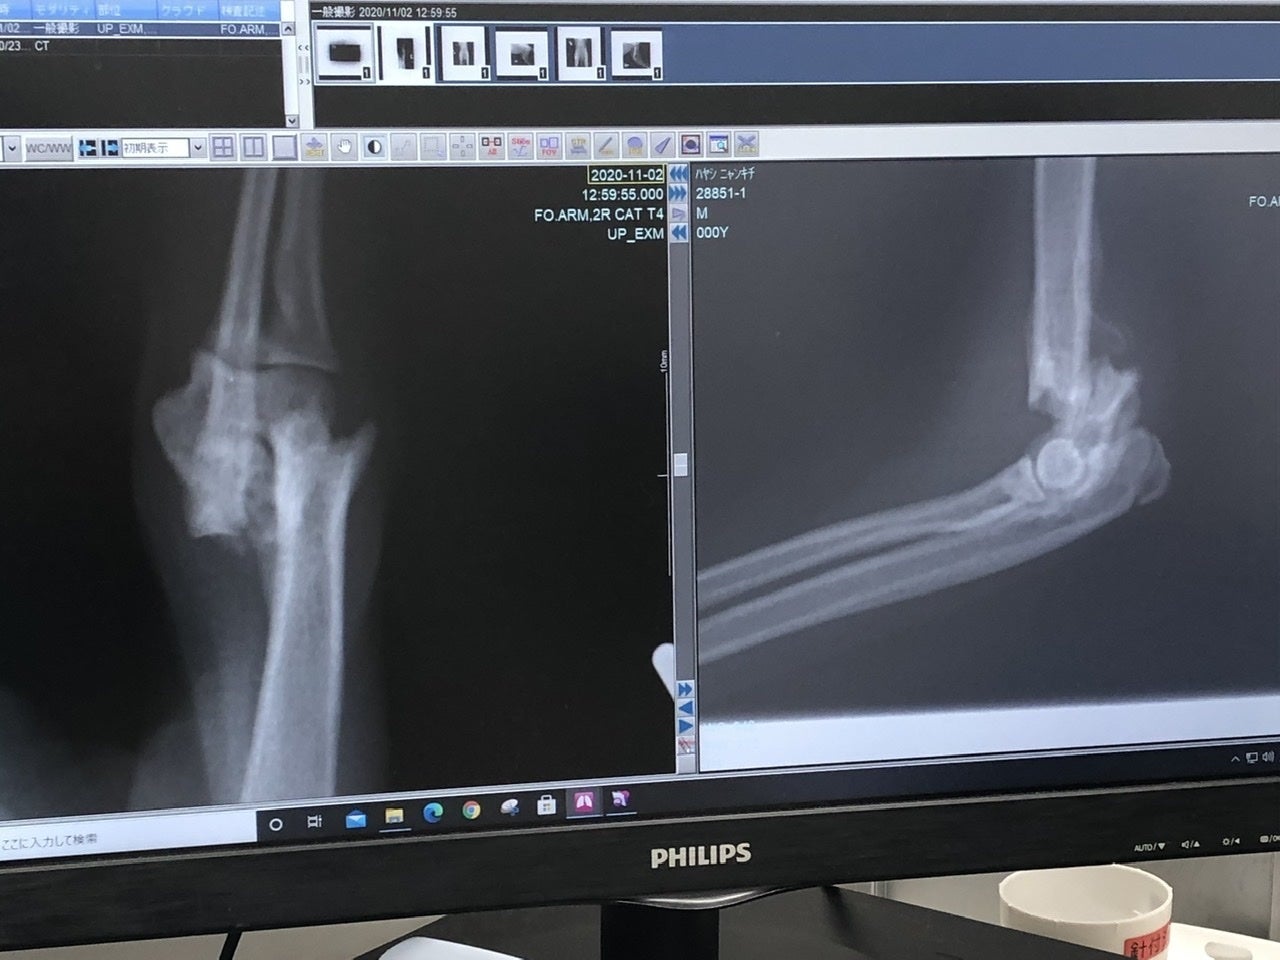

「右上腕部末端(肘)骨折」

の2箇所が骨折していました。

それ以外のキズや臓器系、病気などは無く、強い衝撃が生後間もなく右半分に当たり、骨折したものだと、先生がおっしゃられていました。

再度診察の結果、「右上腕部末端(肘)」が、折れた骨の周辺の肉(繊維)が固まってきており、神経が多く通ってる箇所なんで、逆に傷つける恐れがあるとの事で、今回は見送られました。徐々にですが体重もかけれるのと、後ろが治れば負担も少なくなるとの見解です。